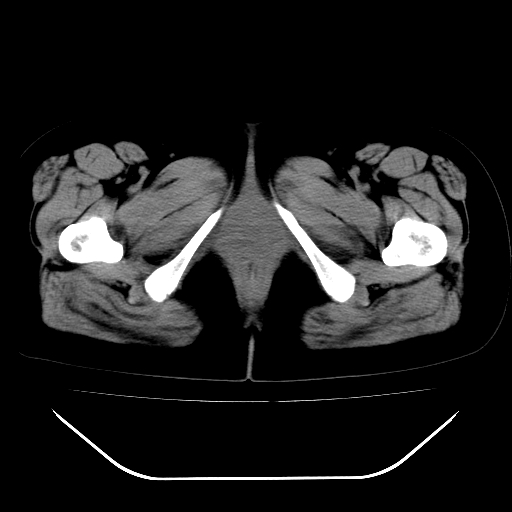

女,48岁,肛门坠胀感一年,肠镜未见异常。

子宫明显增大,形态不规则。多考虑:子宫肌瘤!

子宫明显增大,形态不规则,  盆腔积液 结合临床考虑:1子宫肌瘤, 2  盆腔炎。

道格拉斯窝积液考虑慢性盆腔炎,宫腔少量积液,子宫肌瘤不好说,建议增强。